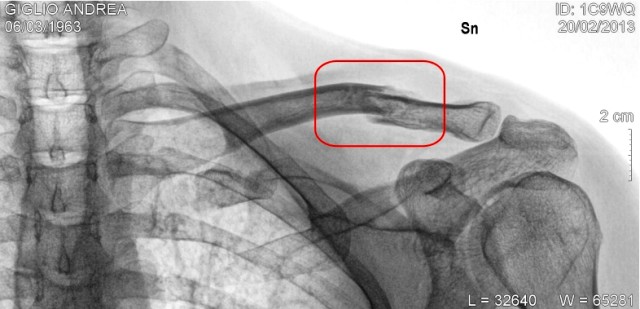

E' una frattura molto frequente nella traumatologia ortopedica, e colpisce indifferentemente sia uomini che donne. Frattura composta 5' metatarso piede sx.